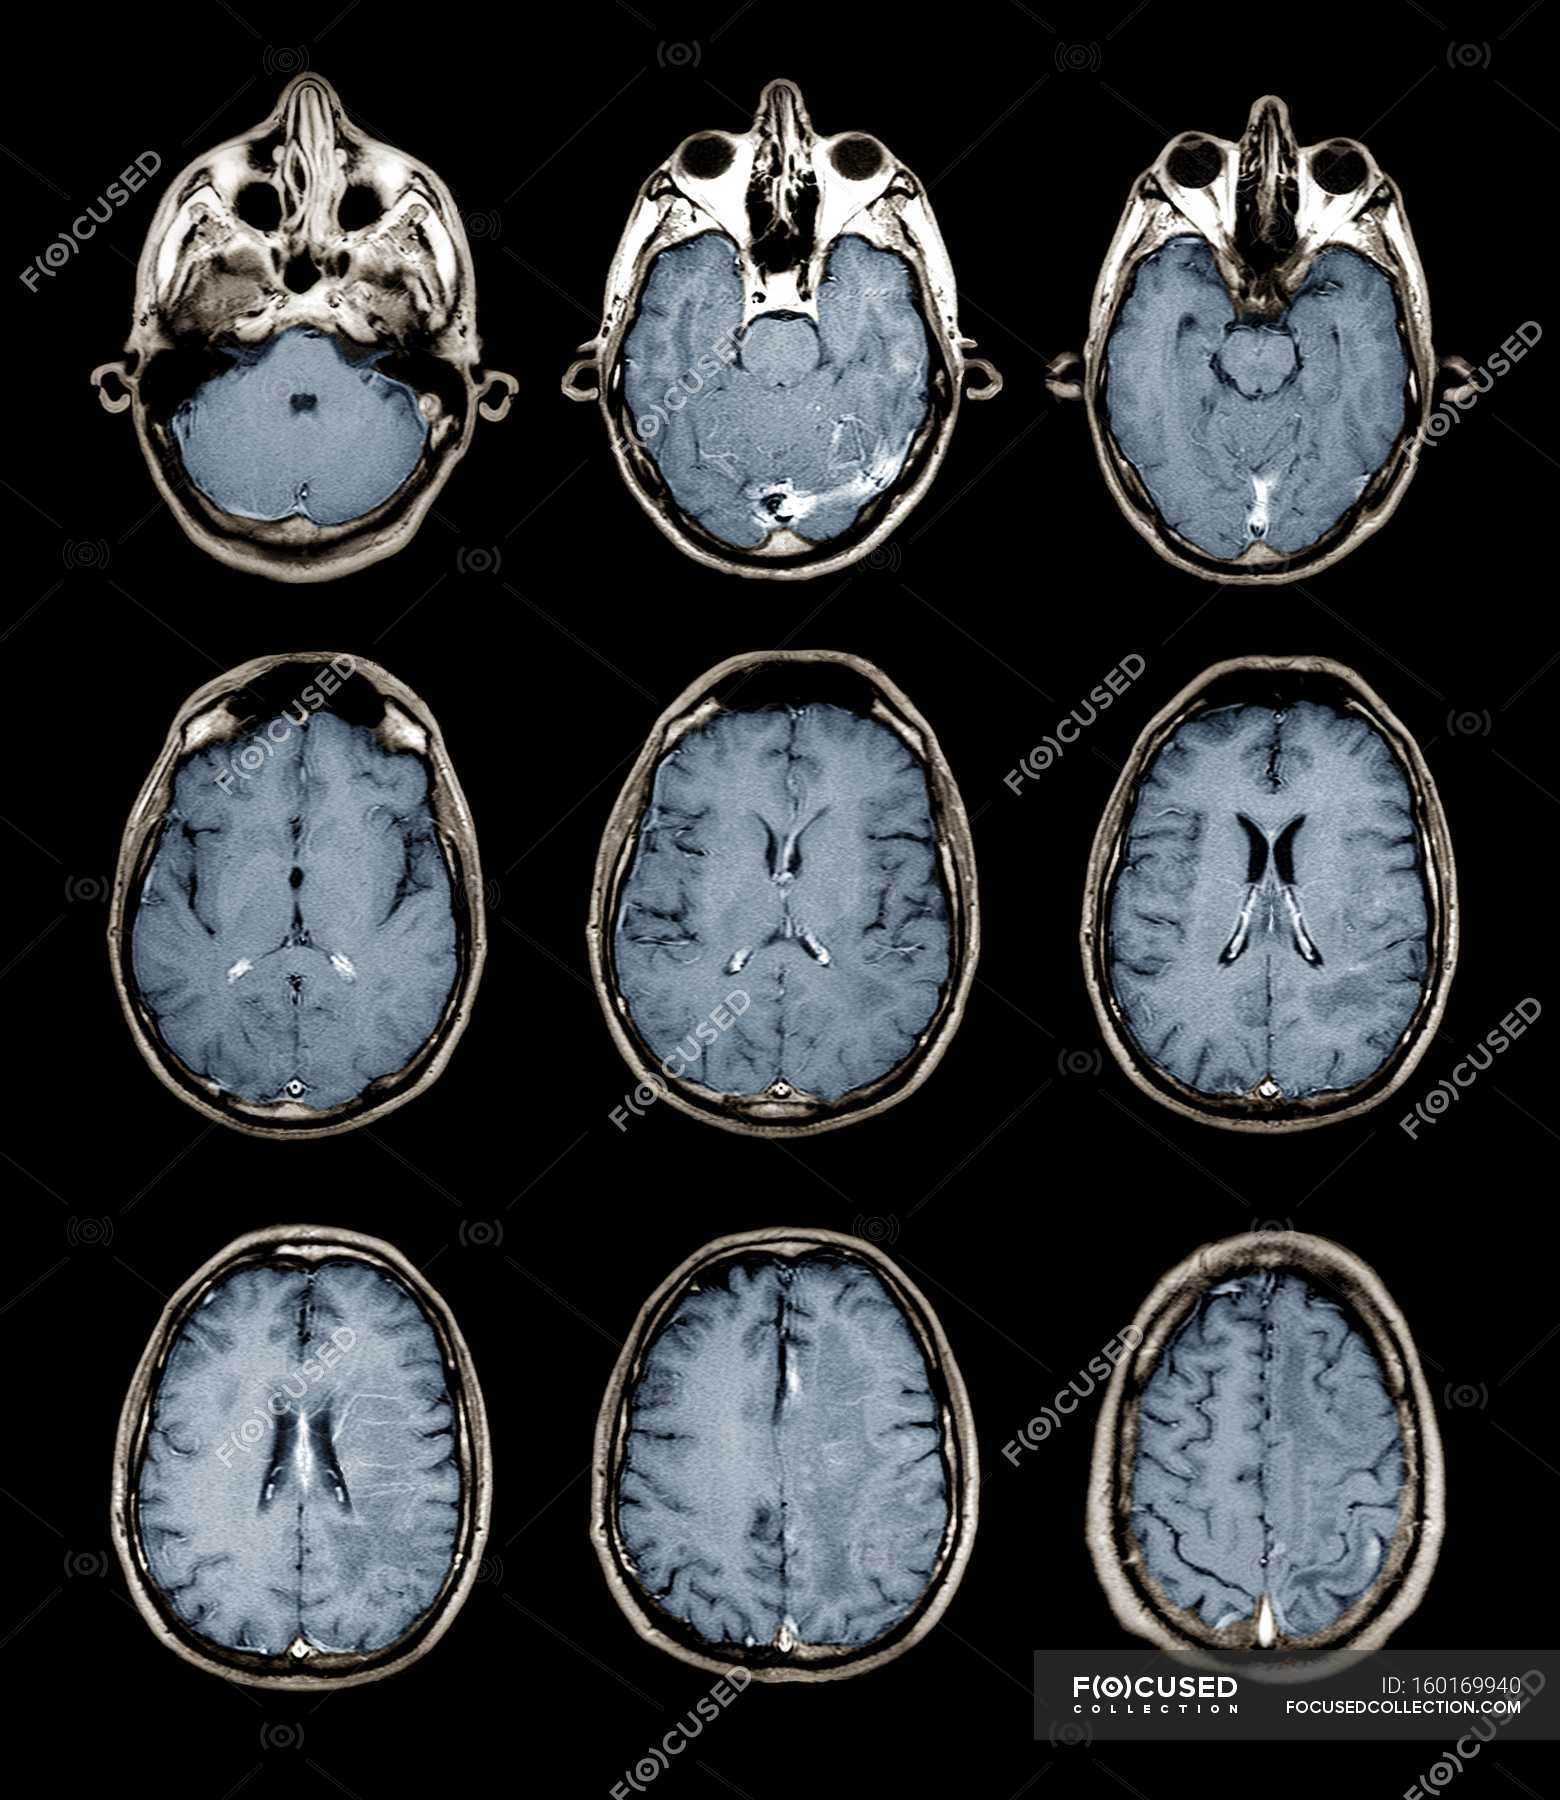

Lista muestra hermosas imágenes de resonancia magnética cerebral normal y anormal dinosenglish.edu.vn para que puedas explorar más en detalle.

resonancia magnética cerebral normal y anormal Pin en NEUROCIENCIAS resonancia magnética de cerebro Resonancia magnética (RM) de cerebro, corte axial ponderado en T2: la … VIDEO Nueva mancha en la Resonancia

Engineer Team : RESONANCIA MAGNETICA Magnetic Resonance Imaging – Clinical Images Hallazgos por resonancia magnética cerebral de nuestro paciente. M, 21 … Imágenes por resonancia magnética anormales como predictoras de mal … Imágenes por resonancia magnética anormales como predictoras de mal … Lesiones en resonancia magnética (RM) del encéfalo y la médula espinal … Pin en Resonancia Magnética del Encéfalo A) Resonancia magnética cerebral (RMC) mostrando infartos en … Caso 1: Edema cerebral visualizado mediante RM. (A) Secuencia T1 plano … Rascacielos dormir pasta tac y resonancia diferencias retrasar … Pin on Apuntes de Enfermería y T.C.A.E Resonancia magnética cerebral secuencia T2, que muestra lesión … Meningitis aguda en la enfermedad de Behçet | Reumatología Clínica Resonancia magnética coronal normal del cerebro Fotografía de stock – Alamy Imágenes de resonancia magnética, la imagen de la cabeza en diferentes … Resonancia magnética cerebral A) protocolo T1 sagital (Caso 1). Se … Resonancia magnética cerebral. Secuencia T1 corte sagital. Atrofia … Resonancia magnética de cerebro, cortes axiales, secuencias T2. Señal … Resonancia magnética de cráneo. A y B) Cortes axiales FLAIR … Resonancia magnética (RM) de cerebro, corte axial ponderado en T2: la … RM cerebral: Interpretación paso a paso | Kenhub Resonancia magnética de cerebro, cortes axiales, secuencias T2. Señal … De Resonancia Magnética De Cerebro Foto de archivo – Imagen de arteria … Top 107+ Imagenes de resonancia cerebral normal – Destinomexico.mx -Imagen por resonancia magnética del cerebro. a) Cortes sagital y axial … resonanCia magnétiCa Cerebral donde se observa hiperintensidad a nivel … MRI (Imagen de resonancia magnética) – Tomografía computarizada de la … Meningioma – NCI Imágenes por resonancia magnética coloreadas del cerebro sano del … Resonancia magnética cerebral en secuencia FLAIR, que muestra lesiones … Contraste resonancia magnetica cerebral – senturinthegreen Relación de los espacios de Virchow-Robin con la enfermedad de … Gliomatosis cerebral – Instituto Nacional del Cáncer Pin en Neurology. Recomendaciones para la utilización e interpretación de los estudios de … Fotografía De La Proyección De Imagen De Resonancia Magnética Del … atmósfera Dirigir Cumplir anatomia resonancia magnetica Desarrollar … Pin en #MEDICINA,#SALUD Resonancia magnética de la nasofaringe De Resonancia Magnética De Cerebro Foto de archivo – Imagen de polilla … Atrofia cortical global de predominio parietal en la Resonancia … Resonancia magnética cerebral | Download Scientific Diagram Neuroblog: Resonancia magnética cerebral en la trombosis crónica de … De Resonancia Magnética De Cerebro Imagen de archivo – Imagen de … ¿Cuáles son los riesgos de la resonancia magnética? – Integra Salud … Resonancia magnética cerebral al decimocuarto día de ingreso: área … Resonancia magnética. Corte axial mostrando área infartada en el … Resonancia magnética cerebral del paciente AV evidenciando lesiones en … -Ressonância magnética de encéfalo mostrando múltiplas imagens … Resonancia magnética cerebral secuencia FLAIR (Fluid Attenuated … Resonancia magnética cerebral con protocolo de epilepsia, en sección … Resonancia magnética cerebral en corte sagital. Se observa una evidente … Resonancia magnética craneal en la que se evidencian lesiones … Logran visualizar el cerebro a detalle más completo tras una resonancia … Así decide el cerebro la severidad de un castigo De Resonancia Magnética De Cerebro, Imagen de archivo – Imagen de … A) Resonancia magnética cerebral; Secuencia Tof: oclusión de arteria … Un estudio asocia la ansiedad con la aparición rápida del Alzheimer IMÁGENES DE 18 F-PR04.MZ PET FUSIONADA CON RESONANCIA MAGNÉTICA … Imágenes por resonancia magnética anormales como predictoras de mal … Tumores de la región pineal – Instituto Nacional del Cáncer Epilepsia: una historia de voces y fantasmas | Neurología Contribución de las imágenes de resonancia magnética por tensor de … Resonancia magnética secuencia T2 plano coronal de quiste epidermoide … Resonancia Magnética Cerebral del paciente: a. Aumento de… | Download … Resonancia magnética cerebral 2022 Síndrome de hemiconvulsión-hemiplejía-epilepsia. Seguimiento de un caso … Enfoque Radiologico: La resonancia magnética permite detectar lesiones … Resonancia magnética craneal T1 con contraste que muestra angiomatosis … guidewiz – Blog Resonancia magnética cerebral, secuencia SWI. Ribete hipointenso en la … resonAnCiA mAgnétiCA de ColumnA Con gAdolinio. Corte sAgitAl en t1 de … SEMANA 12: FUNDAMENTOS DE RESONANCIA MAGNÉTICA NUCLEAR. INDICACIONES Y … DIAGNÓSTICO DE ESCLEROSIS MÚLTIP Magnetic resonance imaging of the brain – Alchetron, the free social … Resonancia magnética de órbitas | Instituto Radiológico Dr. E Castillo Alteración de la marcha en un paciente post-trasplante hepático Resonancia magnética cerebral de un paciente sano (Ay B) y paciente que … Utilidad de la resonancia magnética craneal para el diagnóstico de la … Resonancia Magnética Del Cerebro El Tumor Cerebral Foto de stock y más … De Resonancia Magnética De Cerebro Imagen de archivo – Imagen de … ABDALLA RADIOLOGIA: NEURINOMA ACUSTICO Atrofia cortical global de predominio parietal en la Resonancia … Resonancia Magnética : Producción de la imagen MRI Brain Scan — Stock Photo © Bunyos30 #18724051 Mri (imagen de resonancia magnética) Monitor con imagen de captura de … Tomografía computarizada vs resonancia magnética: diferencia y … Tumores Cerebrales – Unidad de Neurocirugía RGS Resonancia magnética de la columna, sección sagital. Observe los discos … La resonancia magnética, una técnica imprescindible en el diagnóstico … Perfusión Cerebral por Resonancia Magnética | ¿Qué es? ¿Necesita Contraste? Resonancia Magnética Cerebro A: resonancia magnética, T2 coronal preoperatoria; se observa lesión en … Resonancia magnética cerebral — Foto de stock © Bunyos30 #27340623 La resonancia magnética se perfila como detector de mentiras | Futuro … Resonancia magnética cerebral en T1 con gadolinio, cortes axial (a … MRI brain : show brain tumor at right parietal lobe of cerebrum — Stock … NEUROIMÁGENES EN ENFERMEDAD DE PARKINSON: ROL DE LA RESONANCIA …